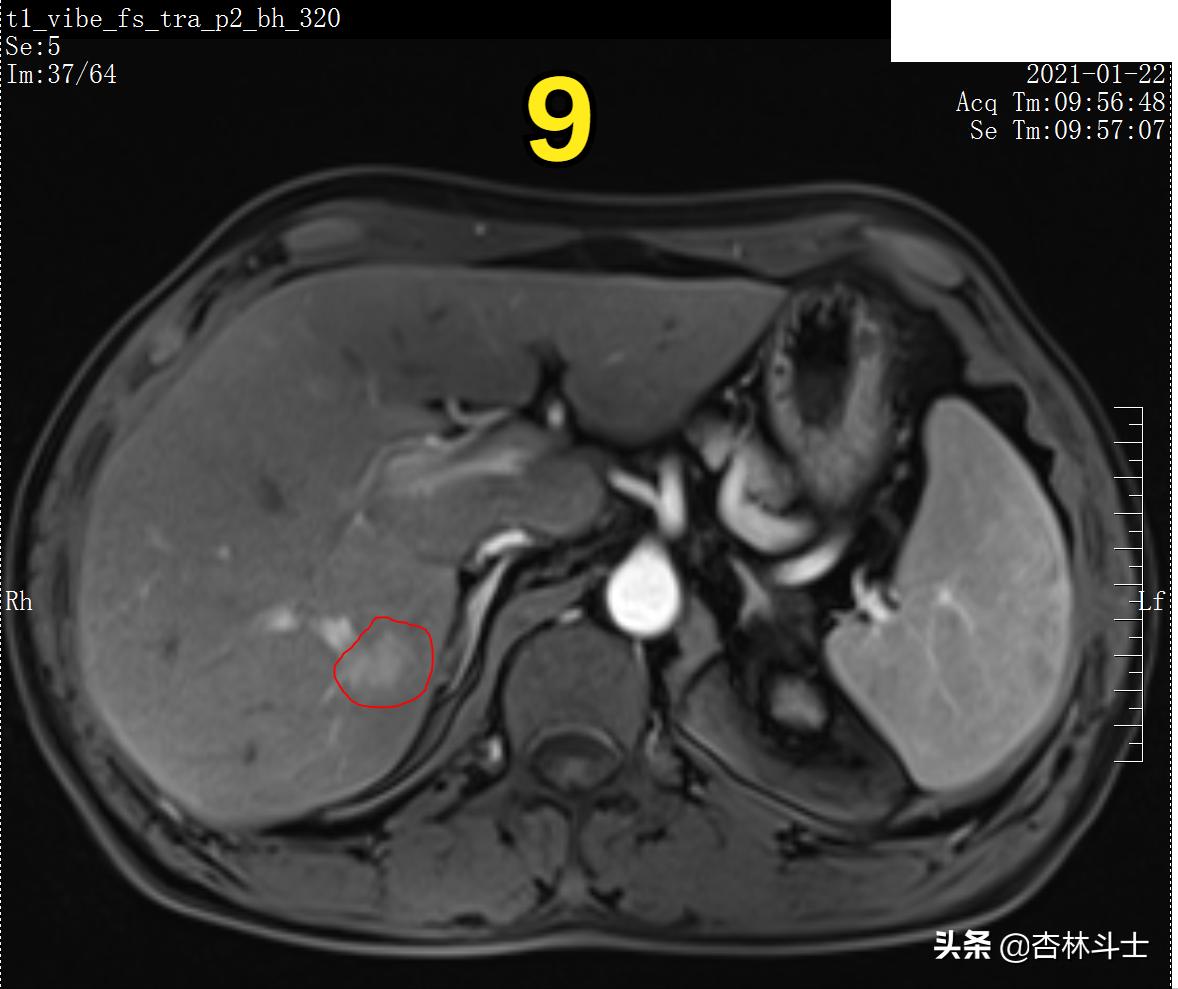

图8 T1压脂动脉期

图9 T1压脂动脉期

图8、9为T1压脂动脉期,可见病灶呈不均匀明显强化。